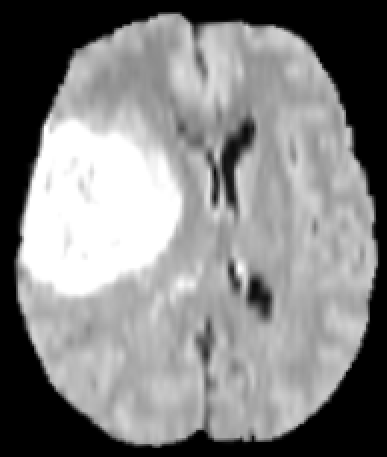

Refer to caption

Figure 1: MRI of a brain with a tumor from different angles